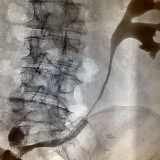

La nefrostomia è una procedura in cui viene posizionato un drenaggio percutaneo attraverso la pelle per drenare l’urina direttamente dal rene verso l’esterno. Questa procedura viene eseguita sotto guida radiologica, in cui il radiologo interventista punta il calice renale e inserisce il drenaggio. È spesso necessaria in caso di danni traumatici o iatrogeni delle vie urinarie, oppure per “mettere a riposo” la via escretrice in caso di ostruzioni gravi.

Posizionamento di Stent Nefro-Vescicale

In alcuni casi, viene posizionato uno stent nefro-vescicale quando il drenaggio esterno non è più necessario o desiderato dal paziente. Questo stent può essere posizionato anche in urgenza, ad esempio in presenza di infezioni gravi, insufficienza renale acuta o in pazienti con un solo rene. La sostituzione periodica degli stent può essere eseguita endoscopicamente dall’urologo o sotto guida radiologica dal radiologo interventista, con una procedura rapida e a basso rischio in regime di day surgery.